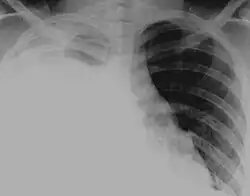

SpecialtyPulmology

Pleural effusions may also develop following the accumulation of other fluids within the pleural cavity; if the fluid is blood it is known as hemothorax (as in major chest injuries), if the fluid is pus it is known as pyothorax (resulting from chest infections), and if the fluid is lymph it is known as chylothorax (resulting from rupture of the thoracic duct).